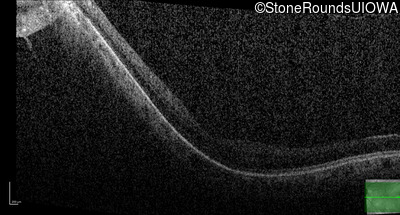

Age at visit: 41 years (Visit 2)

This 41 year old woman was highly myopic as a child and experienced a rhegmatogenous retinal detachment OS at age 20.

The clinical features favoring the diagnosis of Sticker syndrome in this patient include extensive radial lattice degeneration, a personal and family history of rhegmatogenous retinal detachment, a history of cataract surgery before age 30 (and very high myopia before that), arthritis in her knees and hips and a slightly flattened mid-face.